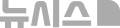

[뉴시스] 뉴질랜드 소년의 장에서 200여 개의 소형 네오디뮴 자석이 제거됐다. (사진=뉴욕포스트) 2025.10.24

이 자석들은 서로 강하게 끌어당기며 장 벽을 압박해 혈류를 차단했고, 그 결과 장 점막 일부가 괴사했다. 의료진은 자석과 손상된 장 조직을 함께 제거하는 수술을 진행해 소년의 장에서 5×2㎜ 크기의 자석 200여개를 회수했다.

소년은 해당 자석을 테무에서 구입한 것으로 알려졌다.